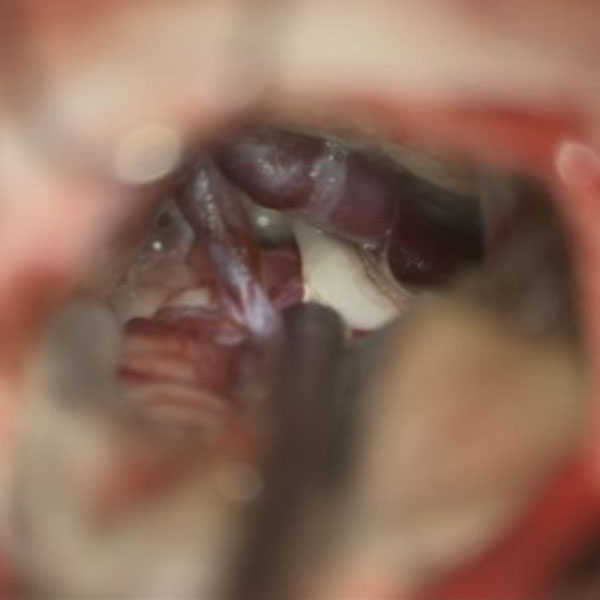

症例 '26年3月

No.

584

'26年3月

50代

三叉神経痛第3枝領域

減圧前

減圧後